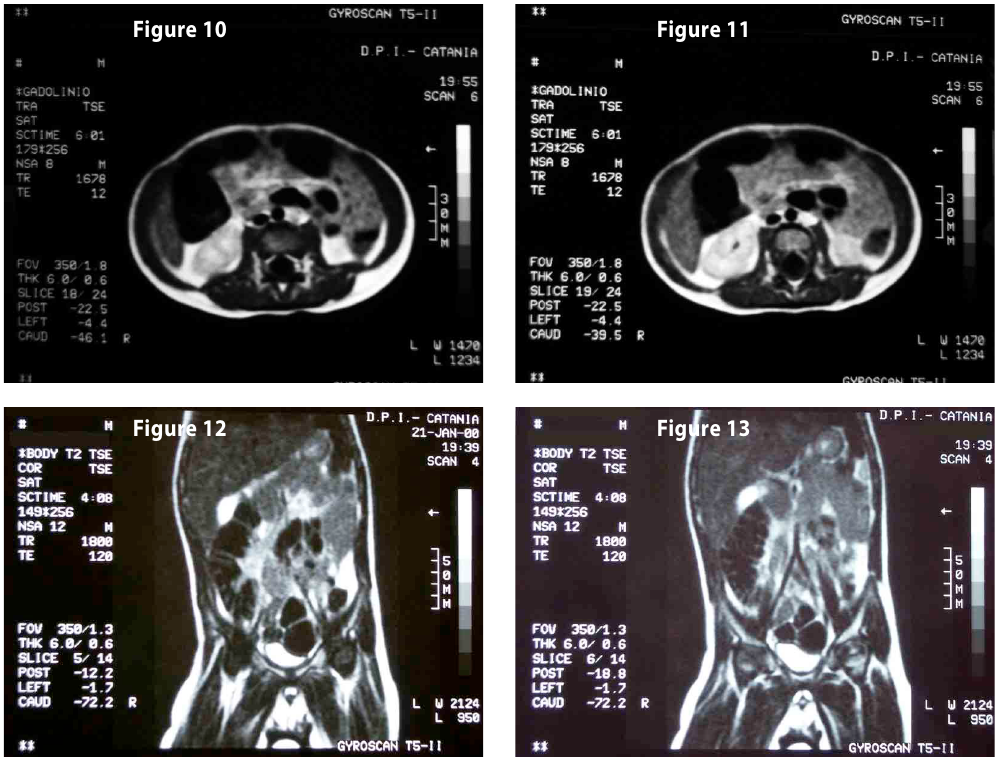

Complete objective response of neuroblastoma to biological treatment.

Figure10-11